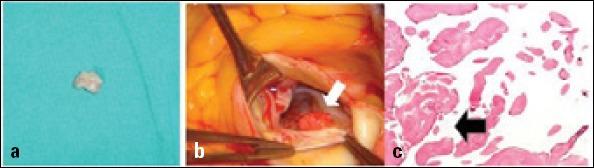

Papillary fibroelastoma associated with congenital heart disease: a coincidental association or a potential new syndrome?

Anatol J Cardiol. 2015 Nov;15(11):951-2. doi: 10.5152/AnatolJCardiol.2015.6371.